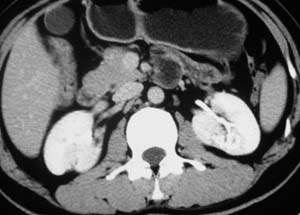

以下是引用子期在2010-3-19 20:47:00的发言:[br]血管畸形的ct增强应该有明显强化,本例并不相符合。本例双肾局部的略低密度影,累及肾盂,局部皮质明显变薄、内陷,增强扫描有轻度的强化,应考虑为炎性病变,患者为年轻男性,累及双肾的感染以结核较常见,可以没有明显的临床症状,尿中有时候也并不能查出什么;肾脓肿常有明显感染中毒症状,本例不符,另外一般的肾盂肾炎或肾小球肾炎通过小便就可确诊,其它还不能排除的是黄色肉芽肿性肾盂肾炎,然而单凭ct一般也很难鉴别。